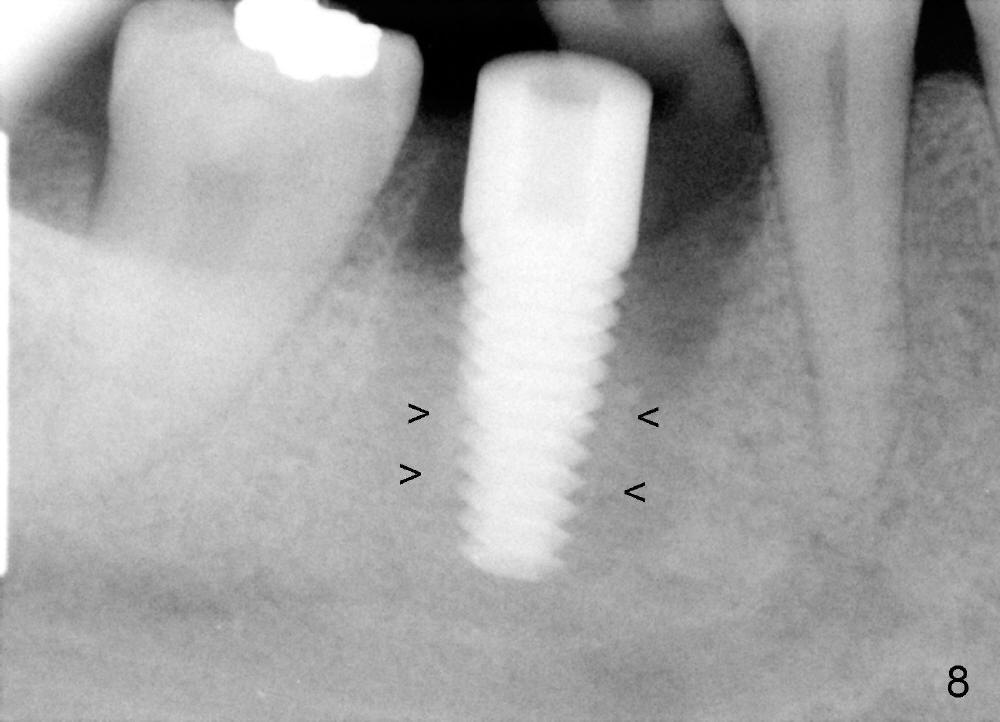

The socket of #30 heals one month after extraction (Fig.1 *). What is unexpected is that the alveolus has started to shrink (follows arrowheads). It is also unexpectedly easy to tap in RT2 (flapless). With insertion of a 2.0 mm pilot drill, PA reveals that osteotomy is not inside the septum (Fig.2 S). Redirecting osteotomy with the same pilot drill leads to insertion into the septum, but the upper end of the pilot drill should be moved mesially in next steps (arrow). With that and treatment plan in mind, combination of osteotomes, Bicon reamers and taps results in right trajectory (Fig.4 * (5x20 tapered tap), Fig.5 (6x17 tapered tap)). Harvested bone (Fig.6) is transferred to the mesial socket and condensed (Fig.7). Insertion torque of 6x17 mm implant is more than 60 Ncm. The lower end of the implant remains in the center of the septum (Fig.8 <). The gingiva contacts the implant tightly (Fig.9, 10) except mesiobucally (Fig.9 <). Periodontal dressing is used to protect the wound (Fig.11,12).